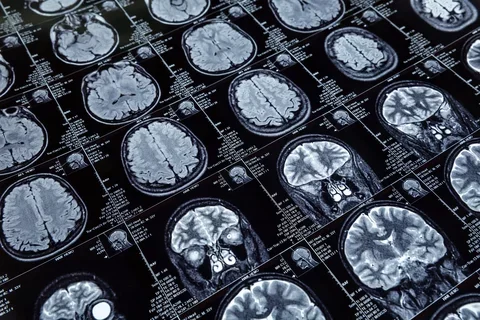

Axonal Swelling in Alzheimer’s Disease and New Tests May Improve the Certainty of Alzheimer’s Diagnosis

Dr. Keith Vossel was interviewed by Healthline about axonal spheroids in Alzheimer’s disease and a new urine test for Alzheimer’s that can improve diagnostic certainty.